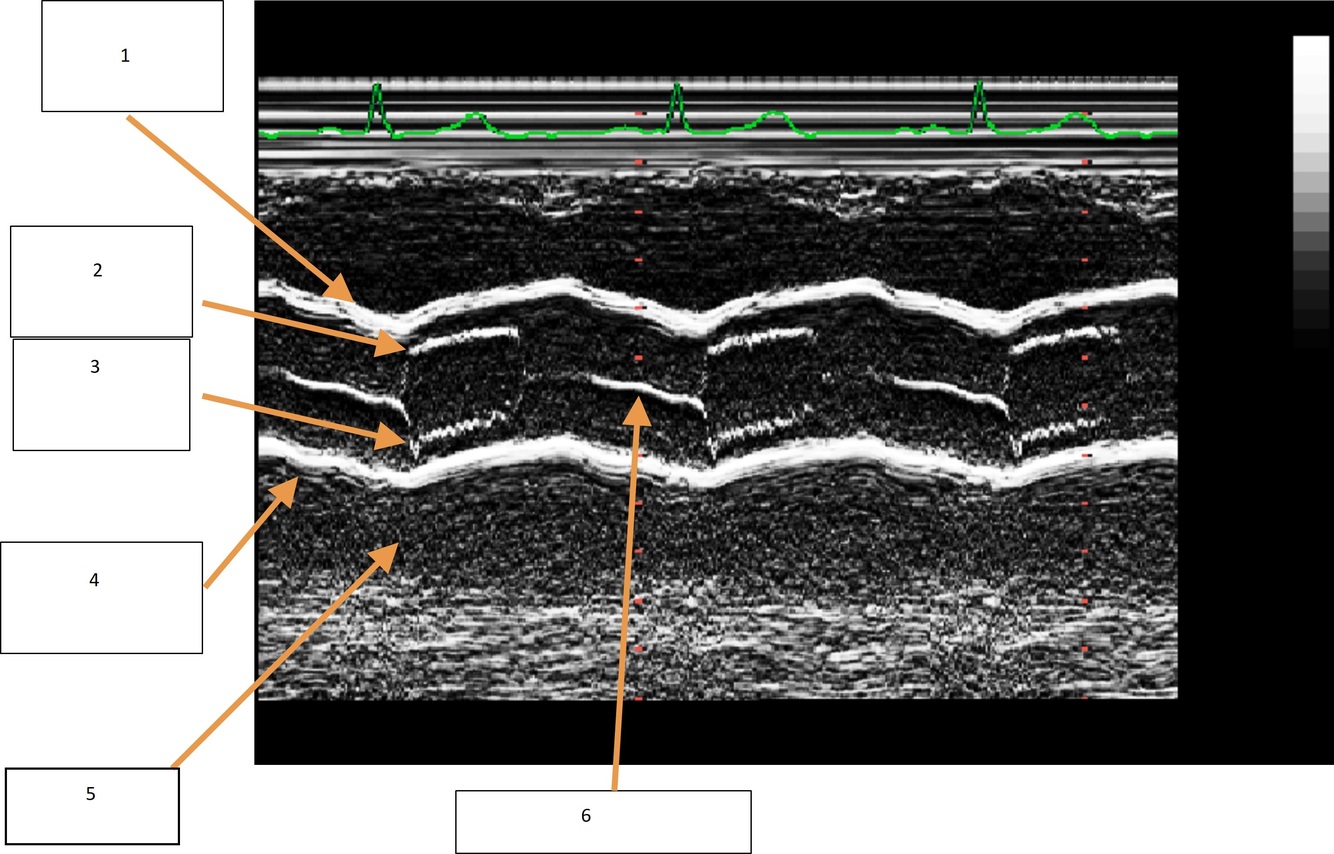

Label the M-mode image of the LV

1. RV 2. LV 3. ED 4. ES

Label the M-mode image of the LV from top to bottom

1. RV Ant. Wall 2. Septum 3. Post LV wall 4. Pericardium

What are the M-mode measurements for LV Diastole? 3

1. IVSd 2. LVIDd 3. LVPWd

What part of the ECG do we take the diastolic measures for LV M-mode?

QRS

What Systole M-mode measurements for LV do we take?

LVIDs

What are some tips to get the measurements for LVIDs?

Measure when the LV is at its smallest

How should we measure the IVSd for LV M-mode?

RV side of the LV septum to LV cavity

How should we measure the LVIDd for LV M-mode?

Posterior IVS to the posterior wall

How should we measure the LVPWd for LV M-mode?

LV cavity to the epicardium